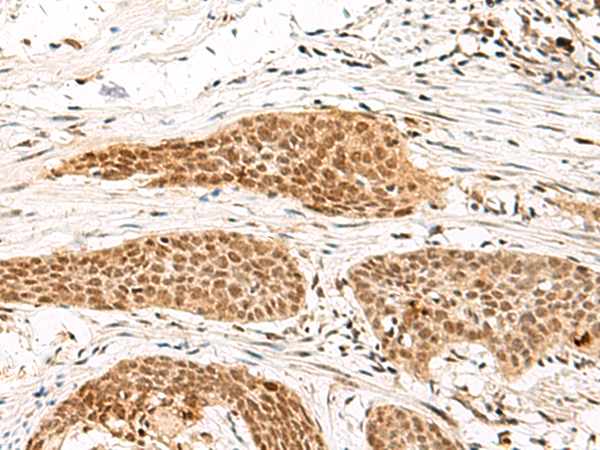

分类: 科研抗体货号: P09872别名: I-MF; I-mfa应用: WB,IHC反应种属: Human, Rat